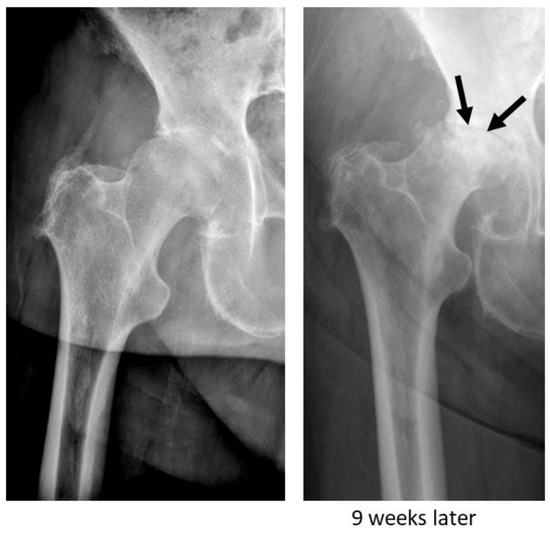

- Zazgyva, A.; Gurzu, S.; Gergely, I.; Jung, I.; Roman, C.O.; Pop, T.S. Clinico-radiological diagnosis and grading of rapidly progressive osteoarthritis of the hip. Medicine 2017, 96, e6395. [Google Scholar] [CrossRef]